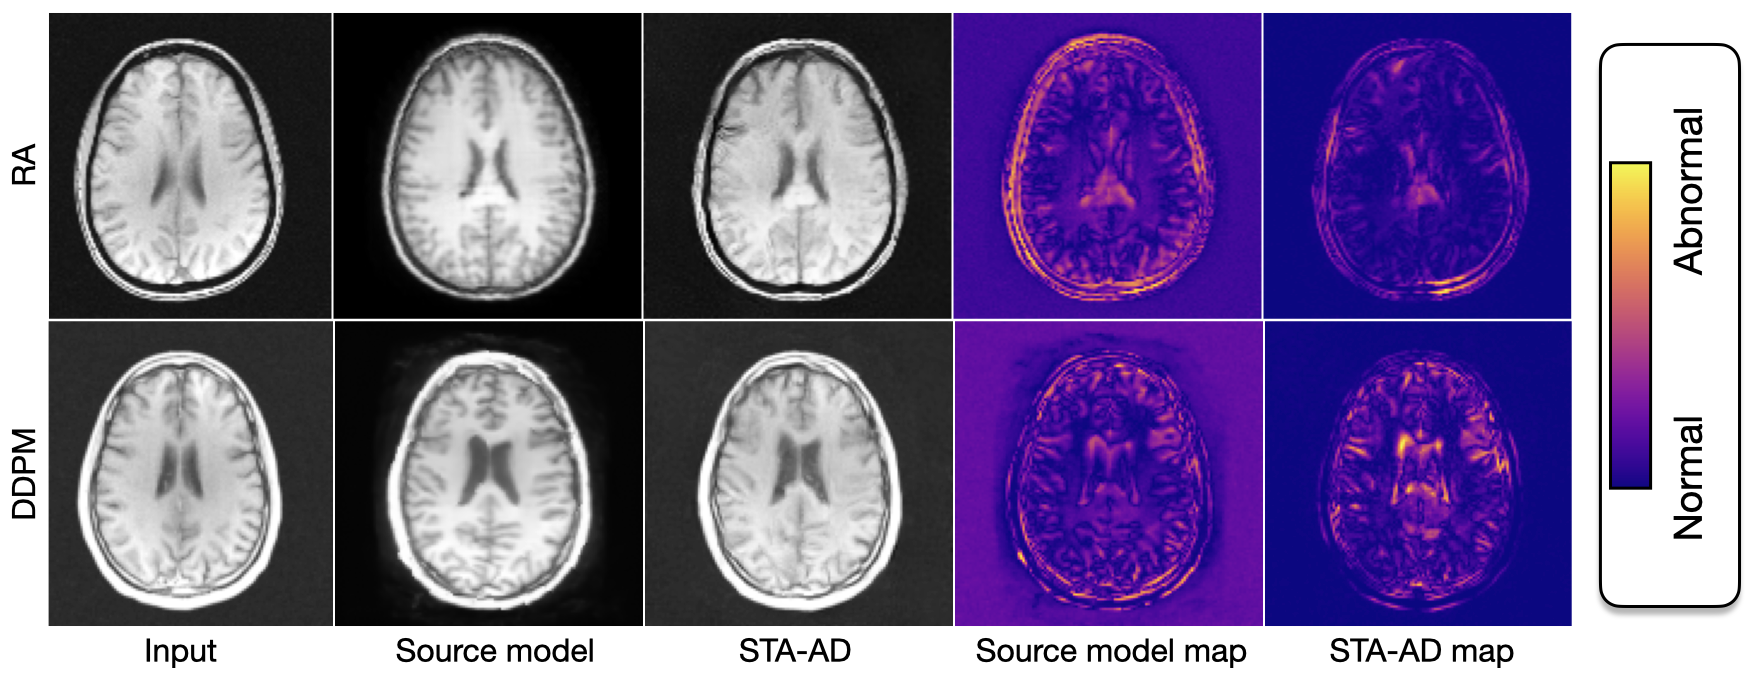

Refer to caption

Figure 3: Comparison on healthy samples from T+subscript𝑇T_{+} dataset. For both backbones, the source models achieve higher false positives due to inaccurate reconstructions. Our approach, STA-AD, through the adapted image, reduces false positive detections in the presented anomaly maps.

3.1 Test-time adaptation on healthy samples

We evaluate whether non-pathological distributional shifts are present between healthy samples from the source distribution and target distributions T+subscript𝑇T_{+} in Table 1. The source model performs well on source data but struggles to generalize to the target domains T+subscript𝑇T_{+}, as evidenced by nearly halved SSIM scores and higher perceptual errors. Similarly, as shown in Figure 3, the RA and DDPM models exhibit increased false positives in their respective anomaly maps. As a baseline, we consider histogram matching. This method achieves slightly higher MAE and SSIM scores than the source model but achieves lower LPIPS scores, which is also evident through the generated image artifacts provided in Supplementary. In contrast, our method consistently improves the MAE, SSIM, and LPIPS scores compared to the source model and histogram matching on both healthy source and pathological target datasets. For the DDPM backbone adapted to the target data, our method achieves improved LPIPS scores but lower MAE and SSIM values. This may be because our method intentionally preserves the original content of the source images, which might result in pixel-wise content differences. We aim to keep the source content and align the source style to the target domain.